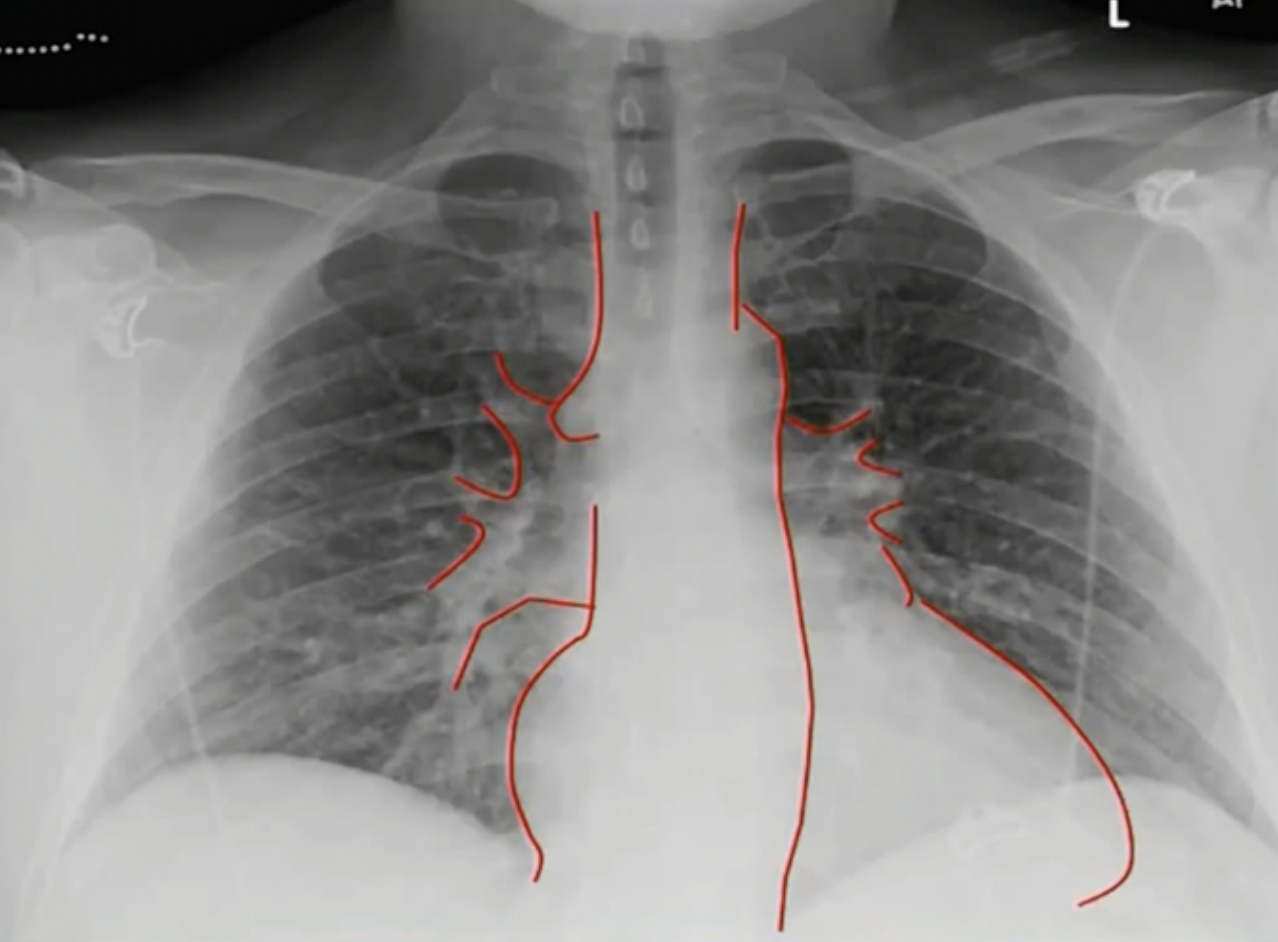

# 正位